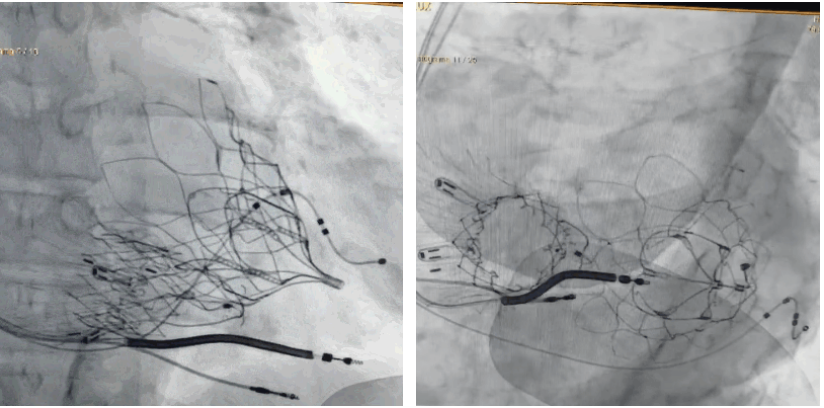

術(shù)后DSA顯示Lux-Valve Plus與Tendyne和ICD無相互影響

手術(shù)在全麻狀態(tài)下進(jìn)行。術(shù)者采用經(jīng)右側(cè)頸靜脈入路的方式將輸送器送入患者心臟內(nèi),在TEE及DSA引導(dǎo)下調(diào)整輸送器頭端角度,使得輸送器與三尖瓣瓣環(huán)平面垂直。在輸送器進(jìn)入右心室后釋放室間隔錨定裝置,而后釋放瓣葉夾持件(2個(gè)耳片結(jié)構(gòu))成垂直狀態(tài)。在TEE及DSA確定夾持件固定至三尖瓣葉根部且位于右室側(cè)后釋放人工瓣心房側(cè)盤片。隨后調(diào)整瓣膜同軸性以及室間隔錨定件位置(貼合室間隔),前推藏針管并固定,進(jìn)而釋放室間隔錨定裝置,并再次確認(rèn)瓣膜位置、穩(wěn)定性及同軸性,合攏輸送鞘后撤出輸送器,完成LuX-Valve Plus人工三尖瓣瓣膜的植入,僅殘余微量瓣周漏。且經(jīng)手術(shù)中心電生理團(tuán)隊(duì)評(píng)估,病人的起搏器和ICD功能沒有受到影響。